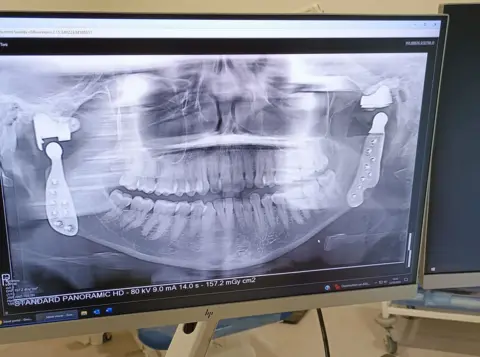

Toni Bull, 35, from Buckinghamshire, was given the nickname Titanium Toni because she has two titanium jaw joints following years of issues, including clicking and reduced movement.

PA MediaMs Bull had her right jaw joint removed and replaced with a titanium one in February 2022. Her left jaw joint was swapped out for a titanium joint this March.